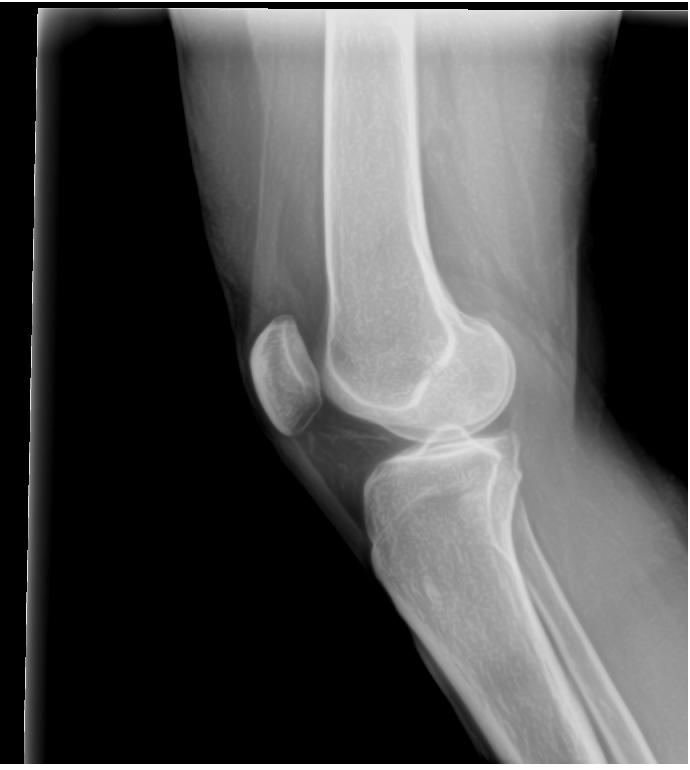

These following two x-rays taken 4-17-13 by Dr. Scott Sheldon, Dwyer Chiropractic, Clarkston, WA:

His interpretation of x-rays: “There is a slight wedge on the lateral aspect of her left knee in the joint space. The left tibia shows anterior rotation on the the AP view. The left fibula has mild lateral displacement. There are no remarkable findings of degeneration. There are no remarkable findings on the right knee.”

Quoting from my office chart note the pertinent findings with the bold type my emphasis: “Musculoskeletal examination demonstrates her to walk about the clinic with assistive devices. She has a Coban wrap involving her left lower extremity from the knee to the ankle. Once removed she does have mild swelling overlying the lateral aspect of the left proximal leg region just below the level of the lateral joint line. There is a trace amount of swelling involving the left ankle….She is tender to palpation overlying the anterior tib/fib ligament, the distal tib/fib syndesmosis, the ATFL and the CCFL….Dorsiflexion and external rotation stress test elicits minimal pain at the ankle but more pain along the mid syndesmotic region. Cotton squeeze test is negative distally but is positive proximally….Examination of the left proximal tib/fib articulation demonstrates evidence of marked increase mobility of the proximal fibula in relationship to the tibia. She is noted to have a posterior and inferior instability pattern. This instability becomes worse with the leg externally rotated and it tightens with the leg internally rotated….X-rays from an outside facility reviewed about the left knee including AP and lateral demonstrates no gross evidence of arthritis changes present. The overall articulation of the proximal tib/fib joint appears to be well aligned….X-rays obtained today of her left ankle in our facility, AP, mortis and lateral views demonstrates the syndesmosis and ankle mortis to be well aligned. There are no signs of fractures or avulsion injuries noted….Outside MRI of left knee is also reviewed, which demonstrates no gross evidence of collateral or cruciate liagment tear or laxity or involvement. The meniscus appears to be intact. Minimal arthritic changes are present. There is mild increased fluid accumulation and swelling around the proximal tib/fib articulation.”